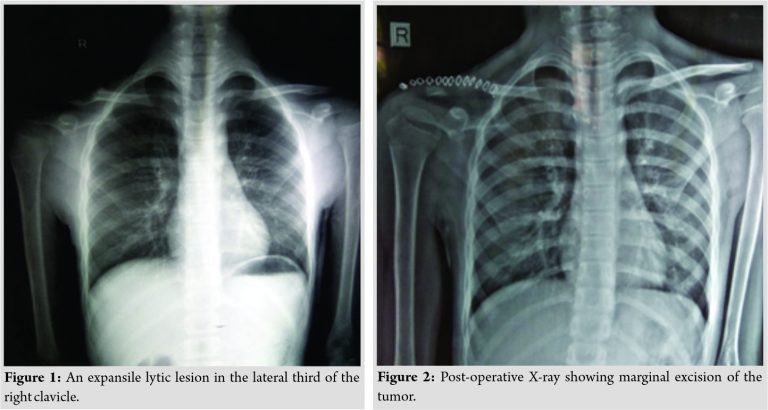

Radiograph at the time showed an expansile bony mass at the lateral fourth of the right clavicle with internal septations with thinning of the cortex and no evidence of periosteal reaction (Fig. 1).

The affected part of the lateral part of the clavicle was resected leaving the thick periosteum intact (Fig. 2). The surgical specimen measuring 4 × 2 × 1 cm showed a multiloculated cyst of about 1.7 cm along with solid areas measuring 1.5 cm. The cyst wall showed focal blackish areas. Histologically, section revealed solid and cystic areas. The cysts were separated by septa and filled with hemorrhage and beneath the surface showed osteoid bone formation and multinucleated giant cells. Stroma showed loosely arranged spindle cells which had vesicular nuclei, inconspicuous to prominent nucleoli, and moderate amount of eosinophilic cytoplasm. Prominent blood vessel proliferation was evident. Pleomorphism and mitotic figures were not seen in the specimen. The overall histological picture was that of an aneurysmal bone cyst.